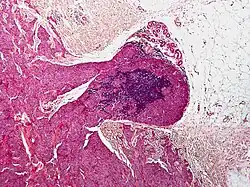

Micrograph of a blue nevus showing the characteristic pigmented melanocytes between bundles of collagen. H&E stain.

Blue nevus